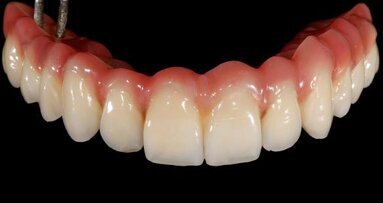

Finally, the designed temporary was sent to the milling unit and produced on a convenient PMMA disc (Telio CAD, Ivoclar Vivadent), resulting in a perfect full-arch bridge about 2 hours later. In this case, using SRAs, a monolithic Telio CAD bridge was produced without any Variobases (Straumann) for the SRAs. Final temporary production steps included characterisation and polishing (Fig. 18).